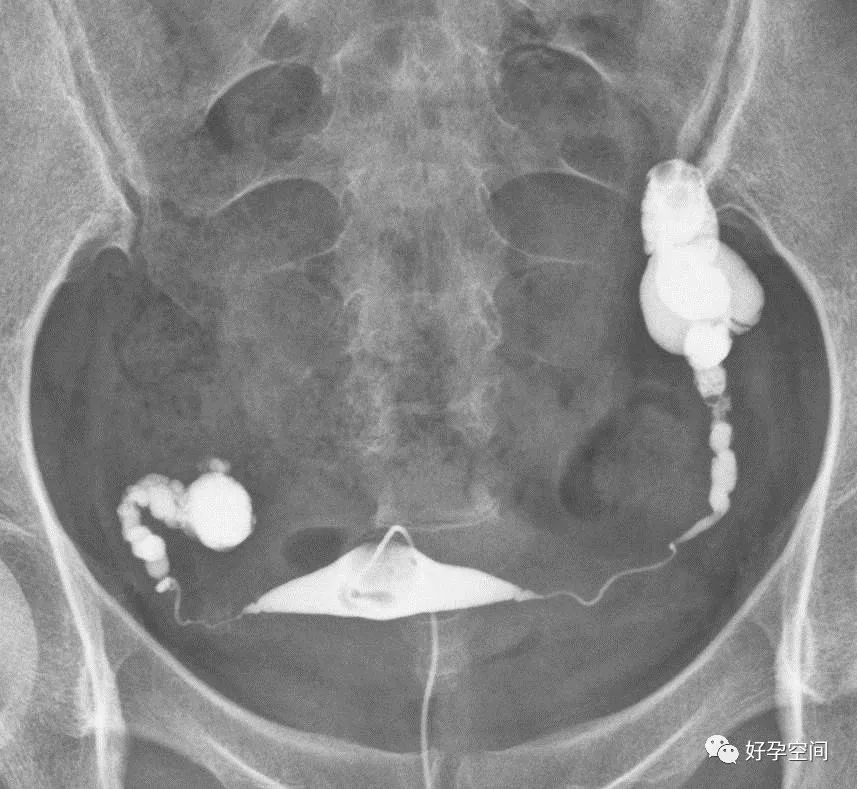

输卵管积水,串珠样改变,功能丧失

输卵管积水,输卵管像风干的腊肠,粘膜近消失,功能丧失